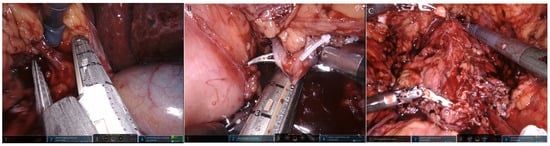

2.2. Robot-Assisted CUTE